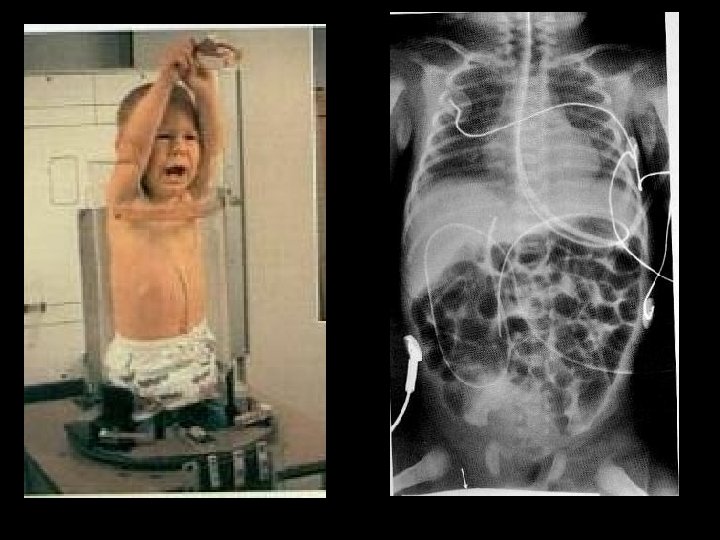

X-rays can provide information about: • Obstructions (blockage) • Tumors • Fractures • Other diseases & illnesses

X-rays can provide information about: • Obstructions (blockage) • Tumors • Fractures • Other diseases & illnesses